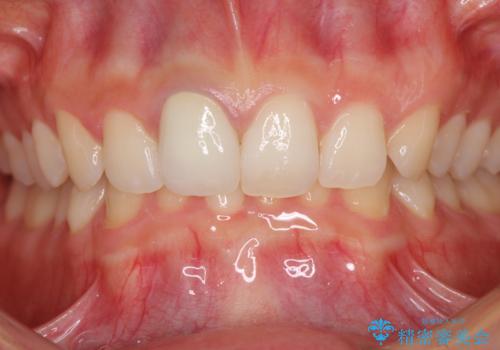

あっという間に気になっていた変色が解決し、早く治療を始めれば良かったとおっしゃっていました。

オーダーメイドタイプのクラウンを選択いただいたので、まるで天然の歯と見間違うほど自然に仕上がり、患者様には大変満足していただきました。